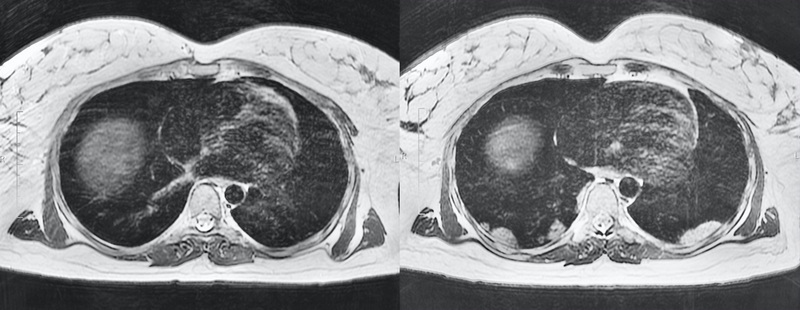

МРТ лёгких беременной пациентки с пневмонией COVID-19

В работе представлен клинический случай 39-летней беременной женщины с респираторными признаками новой коронавирусной инфекции COVID-19. Результаты исследования органов грудной клетки методом магнитно-резонансной томографии (МРТ) показали билатеральное поражение в базальных отделах. Тест на коронавирус методом полимеразной цепной реакции был положительным. Оценка состояния лёгких проведена без потери значимой диагностической информации. Кроме того, отсутствие воздействия ионизирующего излучения позволило избежать высокой дозовой нагрузки на пациентку и плод. Данный случай раскрывает перспективные возможности МРТ в диагностике лёгочной патологии без воздействия ионизирующего излучения, особенно в группах риска (дети, беременные и др.).